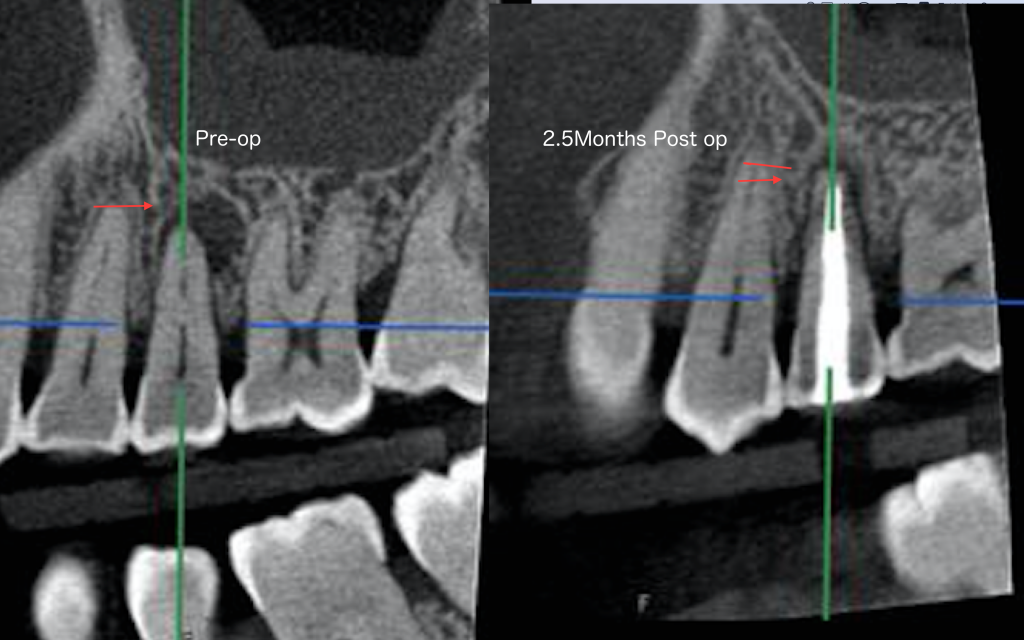

2.5ヶ月にCTを撮影して治癒を確認致しました。骨が見事に再生していることに注目して下さい。

別の角度からCT画像をご覧下さい。

根管治療が成功した結果、排膿路が消え歯周ポケットがなくなりました。